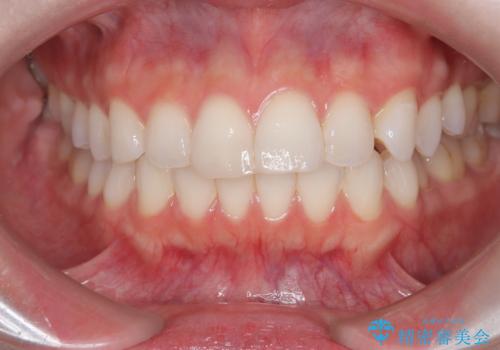

前歯の突出を防ぎながらガタつきを解消。上下左右4番抜歯による審美ワイヤー矯正